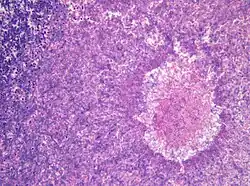

![]() Aspergillus niger. | |||||||||||||

Cerca de 16-20 espécies podem infectar o homem causando morte, sendo as mais comuns A. fumigatus, A. flavus e A. niger. As manifestações clínicas incluem micetomas (infecção subcutânea), reação de hipersensibilidade (aspergilose alérgica), aspergilose pulmonar (que pode conter aspergiloma e ser necrosante crônica) e sua forma mais letal: invasiva generalizada em imunocomprometidos. Injeções de posaconazol podem ser usados em casos de emergência.[2]